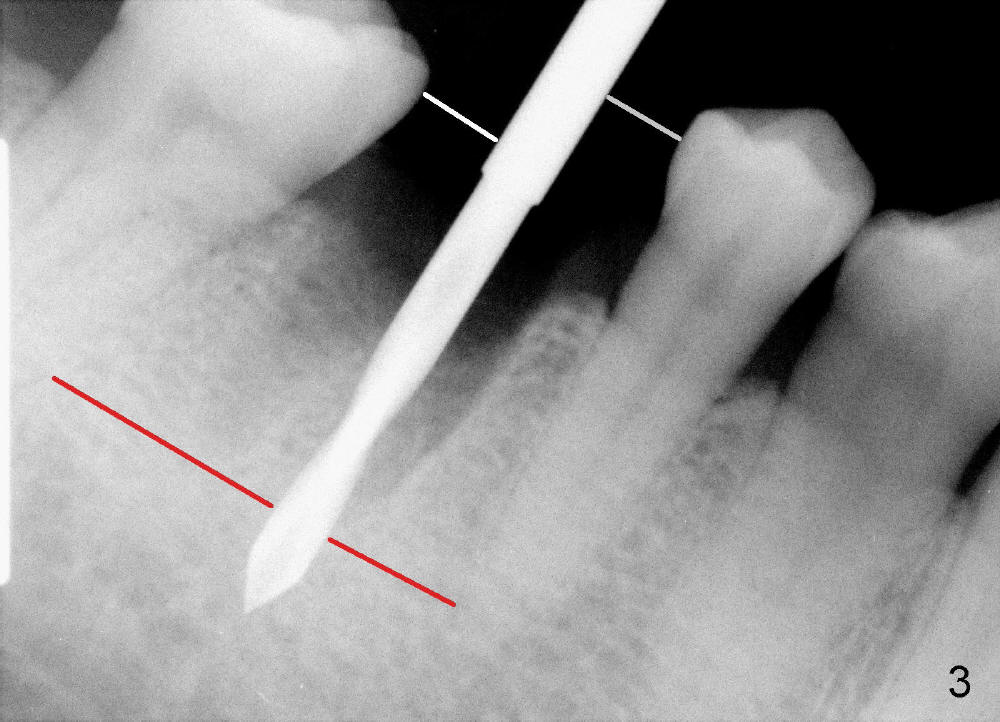

A 47-year-old man has had perio infection in the lower right 1st molar twice (Fig.1,2). Buccal and lingual furca pockets are ~ 9 mm. Following extraction and sectioning the septum, the osteotomy is initiated with a 2 mm pilot drill (Fig.3). Although the drill deviates into the mesial socket, the coronal end is controlled more or less in the middle of the edentulous area (compare white and red lines). Ideally the axis of the osteotomy (Fig.4 red line) should be parallel to that of the 2nd molar and perpendicular to the curve of Spree. The coronal end of the 3.5 mm reamer (Fig.5) and of the 7x17 mm tap (Fig.6 T) remains in the center of the edentulous space. The apical threads of the tap are engaged into the bone for stability (Fig.6 <). When 7x17 mm implant is placed with > 60 Ncm, the mesial socket is obliterated while the density of the distal one increases because of autogenous bone grafting (Fig.7*).